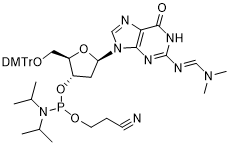

馬鞍山致研生物醫(yī)藥科技有限公司成立于馬鞍山市鄭浦港新區(qū)現(xiàn)代產(chǎn)業(yè)園。公司專(zhuān)注于生物小分子、醫(yī)藥中間體相關(guān)產(chǎn)品的研發(fā)和生產(chǎn),產(chǎn)品主要包括DNA亞磷酰胺單體、RNA亞磷酰胺單體、特殊單體以及按照客戶(hù)要求定制的RNA和DNA,并且公司提供定制合成等方面的研究服...

馬鞍山致研生物醫(yī)藥科技有限公司成立于馬鞍山市鄭浦港新區(qū)現(xiàn)代產(chǎn)業(yè)園。公司專(zhuān)注于生物小分子、醫(yī)藥中間體相關(guān)產(chǎn)品的研發(fā)和生產(chǎn),產(chǎn)品主要包括DNA亞磷酰胺單體、RNA亞磷酰胺單體、特殊單體以及按照客戶(hù)要求定制的RNA和DNA,并且公司提供定制合成等方面的研究服...